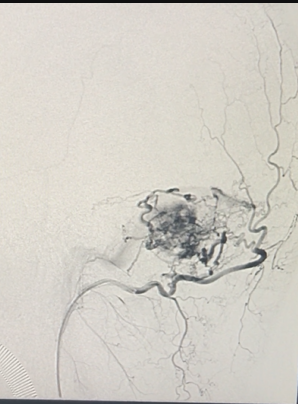

经院内会诊,建议积极术前准备,联合介入科先行超选择性动脉栓塞术+小脑血管母细胞切除术。

介入治疗栓塞瘤体颅内部分供血动脉。

介入手术完成后,行开颅手术治疗。可直接切断经颈外动脉对瘤体的供血。